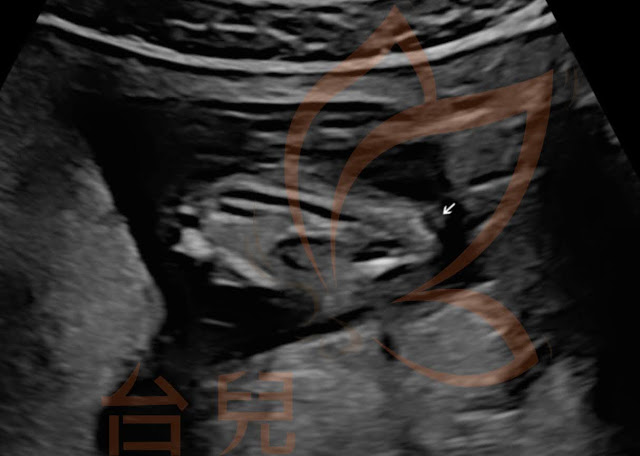

妊娠22週留存的脊椎橫切面動態影像,已可見薦骨骨頭型態異常,皮下異常腫塊延伸至脊髓腔內和神經相連(圖5c)。

關於LDDs此類合併有皮下脂肪腫塊、但沒有小尾巴樣突起或低回音病灶的閉鎖性脊柱裂,產前超音波除了常見延髓圓錐位置明顯較低之外,藉由上述兩個台兒案例回顧,發現其實有機會在各孕期不同的檢查切面下觀察到脊椎骨及脊髓腔形態異常合併皮下組織異常增生。至於適合安排胎兒核磁共振檢查的週數,一般建議在胎兒較大的第三孕期可得較清楚的影像;但若如案例二在中期超音波下已可看到脊椎骨缺失或疑似皮下脂肪腫塊,則不在此限。